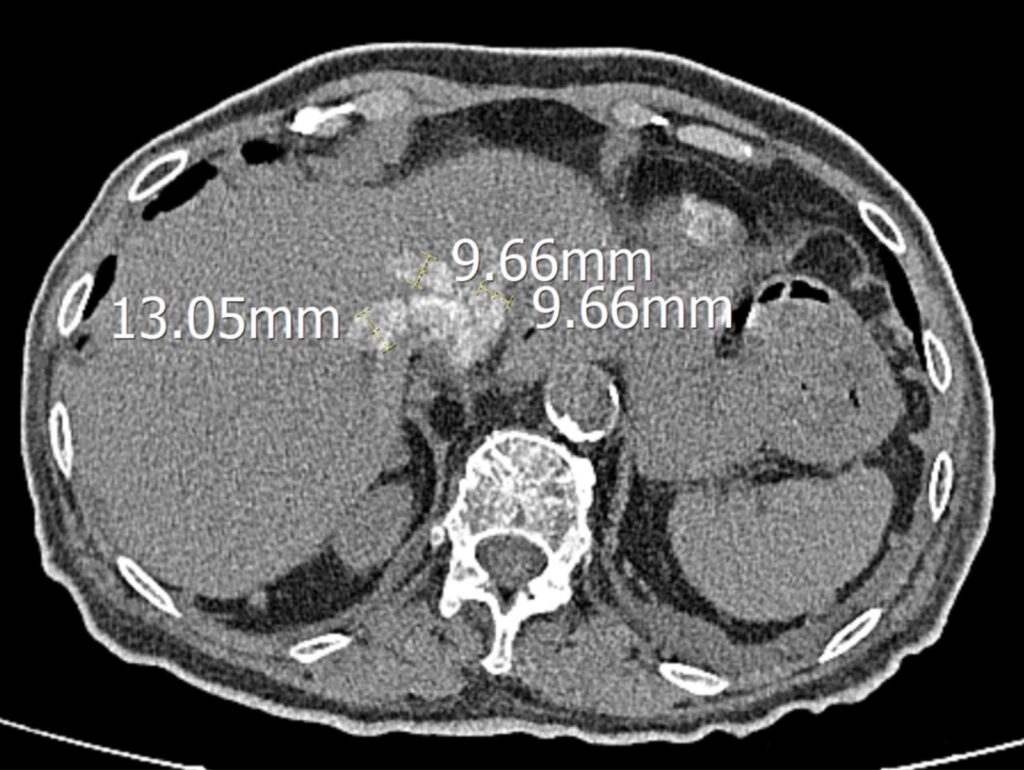

Slika 2. CT prikaz dilatiranih hepatalnih vena s refluksom kontrasta (vidljivo opterećenje desnog srca)

medicinskoj službi Kliničke bolnice Merkur zbog dispneje sa sniženom saturacijom (SpO₂ 80 % na sobnom zraku), tahikardije, očuvanog arterijskog tlaka (120/80 mmHg), znakova zastojne jetre, edema potkoljenica, opće slabosti i smanjene diureze. Od patoloških laboratorijskih nalaza isticali su se povišeni N-terminalni fragment pro-B-type natriuretskog peptida (engl. N-terminal pro–B-type natriuretic peptide, NT-proBNP) (>4800 pg/mL), visokoosjetljivi troponin I (hTnI 173 ng/L), kreatinin 120 µmol/L uz procijenjenu glomerularnu filtraciju (eGFR 37 mL/min/1,73 m²), što je odgovaralo kroničnoj bubrežnoj bolesti stadija G3b/A1. kroničnoj bubrežnoj bolesti stadija G3b/A1 (prema KDIGO smjernicama: eGFR 30–44 ml/ min/1,73 m² uz normalnu ili blago povišenu albuminuriju). Zabilježene su izrazito povišene vrijednosti jetrenih enzima (AST 5054 U/L, ALT 1867 U/L), te hiperglikemija (GUK 23 mmol/L). Pri dolasku bolesnica je bila na terapiji diuretikom Henleove petlje (furosemid) uz suplementaciju kalija (Kalinor), ACE-inhibitorom (perindopril 2 mg), beta-blokatorom (nebivolol 2,5 mg), atorvastatinom 20 mg, levotiroksinom, ipratropijevim bromidom (Atrovent) te inzulinom. Zbog izražene dispneje i tahikardije uz sniženu saturaciju učinjena je MSCT angiografija pluća, kojom je isključena plućna embolija. Nalaz je, međutim, pokazao obostrane plućne infiltrate, pleuralne izljeve te refluks kontrasta u hepatalne vene, što je upućivalo na izraženu kongestivnu komponentu srčanog popuštanja (slika 2).